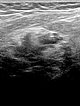

In the 21st week of gestation clear enlargement of the venous malformation on ultrasound with 10.4 MHz linear transducer. Progression of the intramuscular subfascial venous malformation with multiple hypoechoic venous channels. Partly echogenic areas due to clot formation can also be seen now inside the lesion.